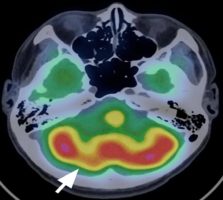

Розсічення хребетної артерії є частою причиною ішемічних інсультів та зустрічається в 1-1,5 випадків на 100 000 чоловік, але така патологія зустрічається в 1 із 10 випадків розвитку ішемічного інсульту у хворих молодиоговіку.

Важливість діагностики полягає в тому, що клініка може починатися від безсимптомних проявів окклюзії, транзиторних ішемічних нападів, але найпоширеніша і найважливіша скарга – біль в голові або шиї, яка зустрічається у 90% хворих. Головний біль має поступовий початок, в основному біль односторонній і включає лобно-скроневу область в поєднанні з запамороченням або запамороченням і порушенням ходи. Порушення структури хребетних артерій (диссекція), які можуть спостерігатися після фізичних навантажень на шийний відділ повоночніка, супроводжуються зменьшенням мозкового кровотоку. По мірі прогресування захворювання можуть спостерігатися виражені запаморочення, атаксія, порушення координації дрібних рухів, аномальне відчуття тулуба, порушення мови. Ортостатичний головний біль класично асоціюється з внутрішньочерепної гіпотензією.